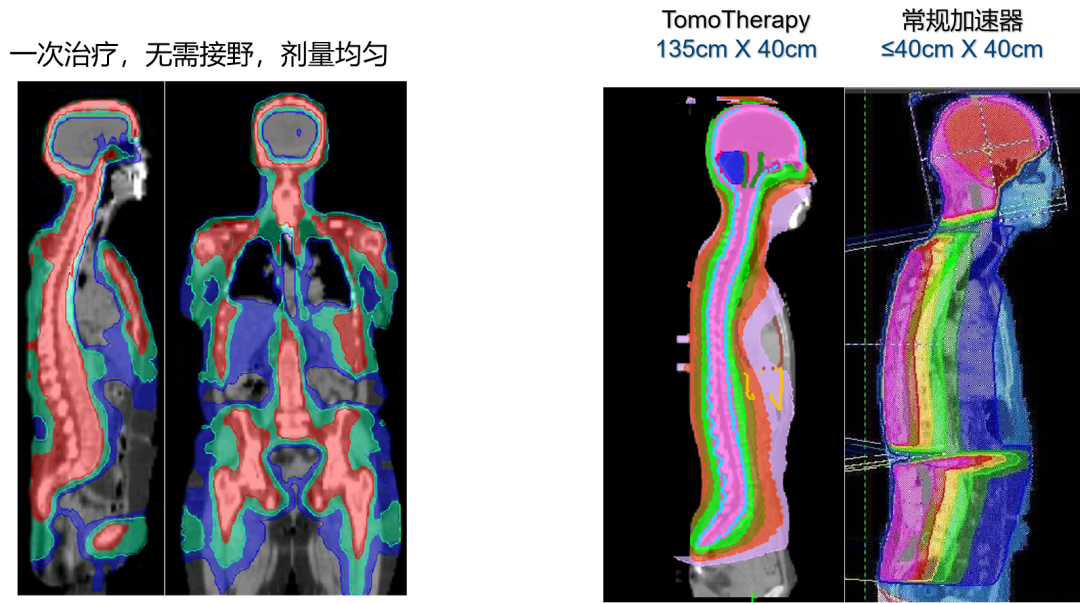

超大照射范围

照射范围达135厘米乘以40厘米,轻松应对全脑、全脊髓等大范围治疗,满足复杂肿瘤的治疗需求。